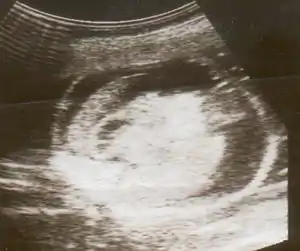

Ultrasound image at 13 weeks, showing the hydrops fetalis.

Hydrops fetalis can be diagnosed and monitored by ultrasound scans.[1] An official diagnosis is made by identifying excess serous fluid in at least one space (ascites, pleural effusion, of pericardial effusion) accompanied by skin edema (greater than 5 mm thick). A diagnosis can also be made by identifying excess serous fluid in two potential spaces without accompanying edema. Prenatal ultrasound scanning enables early recognition of hydrops fetalis and has been enhanced with the introduction of MCA Doppler.[6]